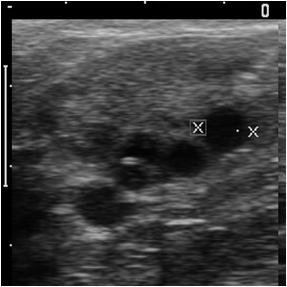

超音波画像診断装置による卵巣画像

また、超音波ガイドを用いることで、牛を屠殺することなく卵巣内の卵子を繰り返し吸引することができます。この技術を経膣採卵(OPU)といい、過剰排卵処理で反応しないような供卵牛を有効に活用する手段として利用しています。